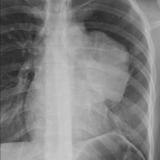

Case 9 Thymoma PA

Date: 04/04/2010

Views: 3167